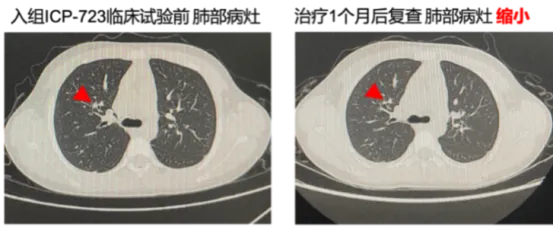

注册研究显示,佐来曲替尼在NTRK融合阳性实体瘤中展现出卓越疗效[7]:总缓解率(ORR)达89.1%,而其中青少年患者的ORR更是达到了100%;疾病控制率(DCR)96.4%,表明几乎所有患者病情均得到有效控制;24个月无进展生存率(PFS)77.4%,总生存率(OS)90.8%,证实了该药能帮助绝大多数患者实现长期缓解。